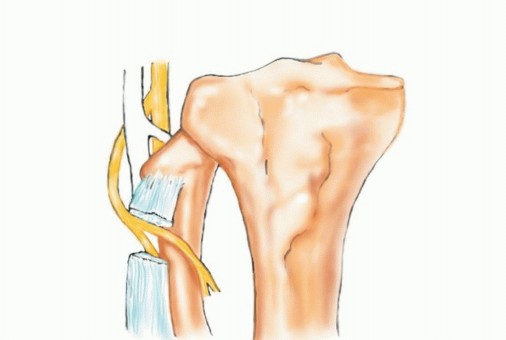

تُعد الشظية القريبة (الرأس والجزء العلوي من العظم) موقعًا رئيسيًا لالتصاق الرباط الجانبي الوحشي (LCL) ووتر العضلة ذات الرأسين الفخذية. هذه الروابط ضرورية لاستقرار مفصل الركبة الجانبي. الأهم من ذلك، أن العصب الشظوي المشترك يلتف حول قاعدة رأس الشظية ليدخل نفق العضلة الشظوية الطويلة، مما يجعله عرضة للإصابة أثناء جراحة الأورام في هذه المنطقة.

- الإجراء: يشمل إزالة الشظية القريبة، وغلاف عضلي رقيق من جميع الأبعاد، وموقع ارتباط الرباط الجانبي الوحشي (LCL). يتم الحفاظ على العصب الشظوي المشترك وفروعه الحركية، ويتم استئصال المفصل الظنبوبي الشظوي داخل المفصل.

- الحفاظ: يتم الحفاظ على العصب الشظوي والشريان الظنبوبي الأمامي عادةً.